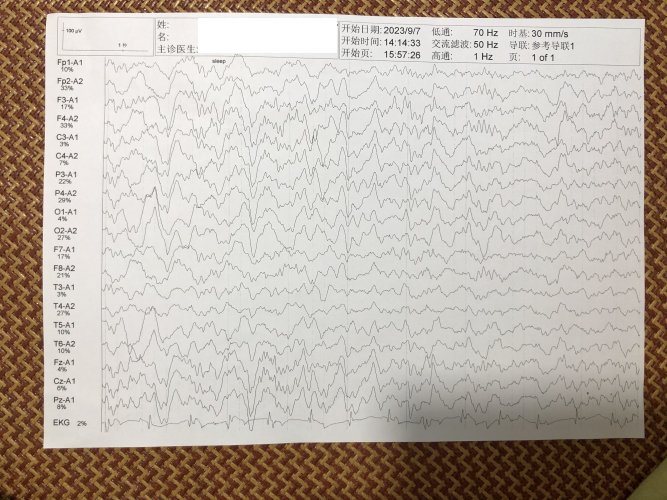

反馈下情况,孩子在国内的医院已经进行过一轮全面检测,没发现什么问题,但是现象是存在的。医生也没什么办法。医生说核磁共振和脑电图没问题,我们也不是很看得懂,各位如果懂的,请指点一下。另外进行了部分基因检测,没发现异常。下一步,我们国庆后打算去更权威的医院去碰碰运气。谢谢各位!